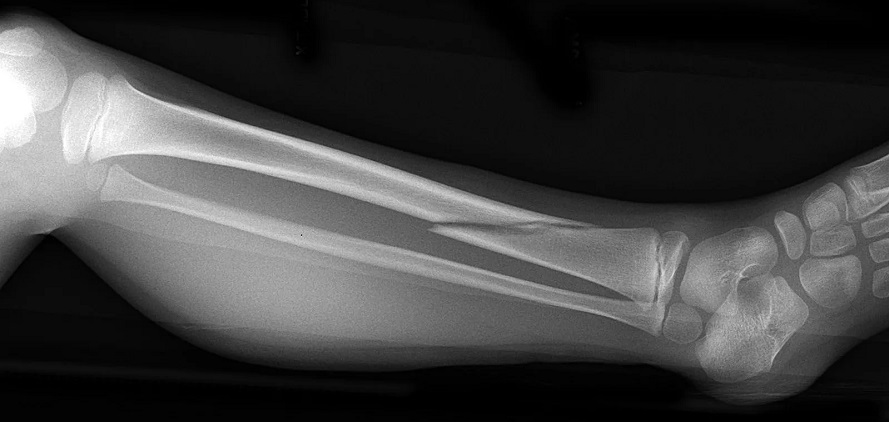

Рентгенография костей голеней в 2-х проекциях (со снимком)

Это рентгенологическое обследования костей голени, которое позволяет увидеть строение и структуру, а также исключить травматическую патологию (переломы) и воспалительные изменения, новообразования.

На снимке рентгена голени, как на черно-белом фото, видно расположение костей голеностопного сустава. Также визуализируется их соединение, хрящевая ткань. Переломы сустава будут визуализироваться как затемнения на белом фоне кости. Опухолевидные злокачественные новообразования также определяются как затемнения, но имеют нечёткие границы.

Иногда, чтобы наиболее чётко составить картину патологии, снимки голени делают сразу двух ног, даже если поражена только одна. При сравнении снимков, их симметрии бывает проще найти отклонение и поставить диагноз.